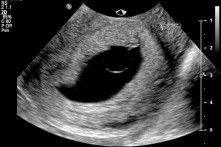

Inilah ultrasound scan rahim ibu yang sudah hamil hampir 3 bulan. Di dalam rahimnya ada kantung kehamilan yang mengandungi air ketuban (air akan kelihatan hitam melalui imbasan ultrasound scan), tetapi tiada janin yang terbentuk di dalam kantungnya. Dari permulaan kehamilan lagi memang tidak ada janin. Inilah yang dinamakan kehamilan tanpa embryo, atau anembryonic pregnancy. 40% wanita yang mengalami keguguran ada kehamilan tanpa embryo. Ada ramai juga yang walaupun ada pembentukan janin, tetapi janin itu tidak normal dan gugur. Sebabnya ialah terdapat kerosakan baka DNA kepada benih telur atau sperma, yang apabila dipersenyawakan tidak boleh menjadi. Walaupun kita manusia yang sihat, bukan semua benih kita sempurna. Tetapi, banyak kes sebegini, keguguran tidak selalunya berlaku dengan serta-merta, sebab itulah bila kita buat ultrasound scan 8 minggu sehingga 12 minggu kehamilan, kantungnya sudah besar tetapi kosong, dan keguguran masih belum berlaku. Pada hakikatnya, untuk kehamilan yang sihat, kita sudah boleh melihat janin terbentuk melalui ultrasound scan sejak 5-6 minggu kehamilan lagi dan boleh lihat denyutan nadi jantung janin. Sudah terlalu banyak kali, saya jumpa kes sebegini bila ibu-ibu hamil datang ke klinik berjumpa dengan saya. Kebanyakannya akan mengalami keguguran dengan sendirinya sebelum 3 bulan. Mereka datang ke klinik untuk ultrasound scan kerana sudah mula melihat sedikit pendarahan menandakan proses keguguran sudah bermula. Mereka tanya saya, adakah sebabnya mereka makan buah nenas semalam, adakah sebabnya mereka minum air kelapa minggu lepas, adakah sebabnya mereka minum air tebu bulan lepas. Adakah sebabnya mereka angkat benda berat pagi ini. Adakah rahim tidak kuat. Jawapan saya ialah TIDAK, Puan. Puan tidak bersalah. Tiada makanan yang menyebabkan masalah ini, dan kegiatan fizikal anda tidak menyebabkan masalah ini. Ini bukan sebab rahim tidak kuat. Sebab itulah saya kata, jangan salahkan diri sendiri. Sebab itulah saya berkata kepada semua orang lain, jangan mencari kesalahan wanita yang mengalami keguguran. Jangan buat fitnah kepada buah nenas. Pada hakikatnya, sudah memang pun kehamilan itu tidak boleh menjadi, sebelum ibu itu makan buah nenas lagi. Banyak penjelasan yang saya sudah sampaikan dalam program #TanyaDrImelda Episod 3, tentang keguguran dan kenapa ia berlaku.